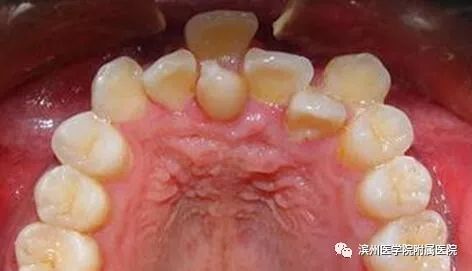

李奶奶的宝贝孙子6岁半了,上颌前面的两颗门牙已经替换了三个多月,可是两颗新牙间缝隙不见变小,反而越来越大了,远没有乳牙长得那么整齐。孙子门牙有大缝这事最近让李奶奶一直着急上火,平日总挂在脸上的笑容也不见了,今天一大早就带着孩子到滨州医学院附属医院儿童口腔科检查。儿童口腔科的医生经过专科查体并配合X线检查,发现是孩子的两颗新长门牙之间有一颗多生牙在作怪。

看完这些,大家对多生牙有所了解了吧,正如上面所讲,如果是在替牙期,多生牙的位置会阻碍正常新牙的萌出通道,导致对应恒牙的萌出位置发生异常,例如牙齿发生扭转、倾斜、拥挤或牙缝过大甚至不能萌出。而且,多生牙奇怪的外形也会严重影响小主人口腔美观及心理健康;也有可能导致含牙囊肿的发生,若无视它继续生长,骨质逐渐向周围膨胀,则会形成面部畸形。